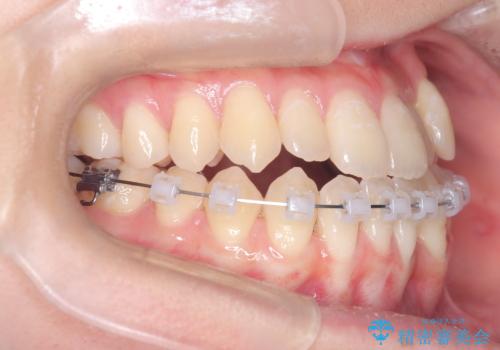

安全かつ確実に抜歯スペースを閉じ、咬み合わせを完成させるため、マウスピースから**ワイヤー矯正(マルチブラケット装置)**へ切り替えるリカバリープランを提案しました。

装置の変更と歯肉への配慮: ワイヤー矯正は歯の根(歯根)を平行に移動させる「歯体移動」を得意としています。本症例では、歯肉退縮を防ぐために、歯の傾きを精密にコントロールしながら抜歯スペースを閉じる必要がありました。ワイヤー装置を用いることで、インビザラインでは難しくなっていた三次元的な細かい調整を可能にしました。